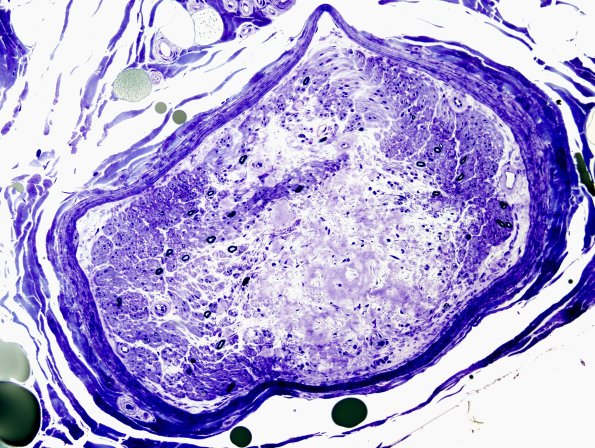

2E1,2 Toluidine blue stained sections of plastic-embedded sural nerve biopsy material shows severe loss of small and large myelinated axons. The amyloid spreads throughout the endoneurium. (Plastic sections)